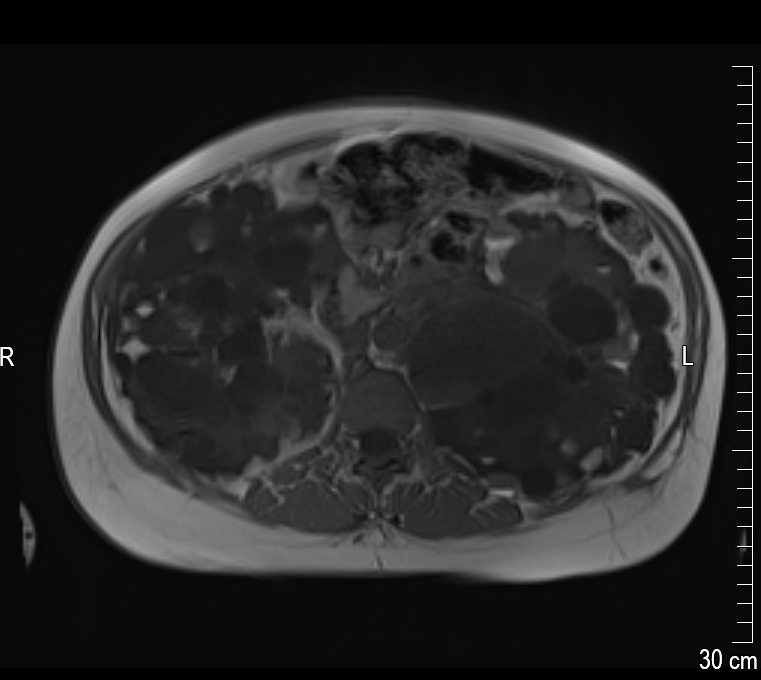

Die linke Niere ist circa 25 cm lang. Der große weiße Fleck unten ist eine der größten Zysten mit einer Länge von circa 8 cm. Die Niere ist so voluminös, dass sie eine richtige Beule ausformt. Die ist tatsächlich an meinem Körper sicht- und spürbar! In der rechten Niere befinden sich kleinere Zysten, dafür – so sieht es auf dem Bild aus – viel mehr als in der linken Niere. Alle anderen inneren Organe müssen den Nieren weichen – was mittlerweile zu starken Magenproblemen und teilweise auch Atemnot führt.

Es führt kein Weg mehr daran vorbei: Ich muss die linke Niere operativ entfernen lassen. Um Platz zu machen für ein mögliches Spenderorgan. Und um meinen Körper allgemein etwas zu entlasten.